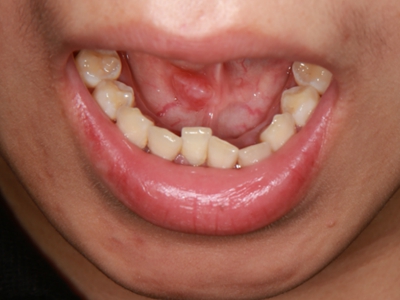

舌尖

圆疙瘩

外渗性黏液囊肿靠近舌尖部位有圆形疙瘩图

外渗性黏液囊肿患者的舌头近舌尖部位出现一个黄豆大小的圆形疙瘩,明显突出于正常舌面,质地柔软,疙瘩破溃后流出黏稠的白色液体,且反复发作。